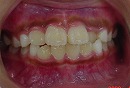

矯正前 矯正後

矯正前の写真を見ると、

上の前から2番目の歯だけ咬み合わせが上下逆になっています。

矯正後は、上下の咬み合わせが改善しています。